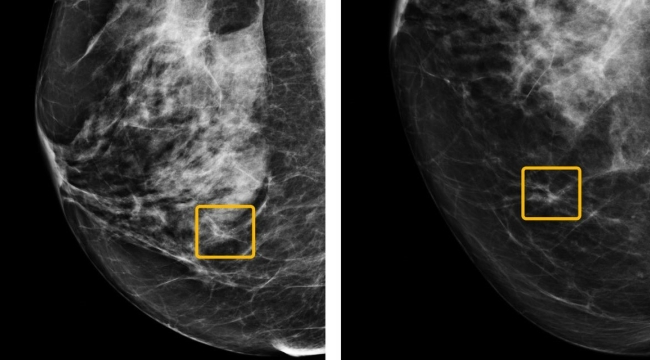

Google, meme kanserinin teşhisinde radyologlardan daha iyi sonuçlar elde eden yapay zekasını kanser tespiti ve radyasyon tedavisi cihazları üreten tıbbi cihaz geliştiricisi iCAD'e lisansladı.

Google, iCAD’e lisansladığı yeni teknoloji üzerinde yıllardır çalışıyordu. 2020 yılında yayımladığı araştırmasında da geliştirdiği yapay zekânın meme kanseri tespitinde radyologlardan daha iyi performans gösterdiğini ortaya koymuştu. Öyle ki yapay zekâ, yanlış "negatif" sonuçları %9,4; yanlış "pozitif" sonuçları da %5,7 oranında azaltmıştı.

iCAD bünyesine geçen yeni yapay zekâ ise şirketin mevcut araçlarına entegre edilecek. Bunlardan birisi, şirketin “ProFound” yapay zekâsı olacak. Halihazırda 3D tomosentez mamografiyi analiz eden yapay zekâ, Google’ın araştırma modeliyle daha doğru sonuçlar sunabilecek.